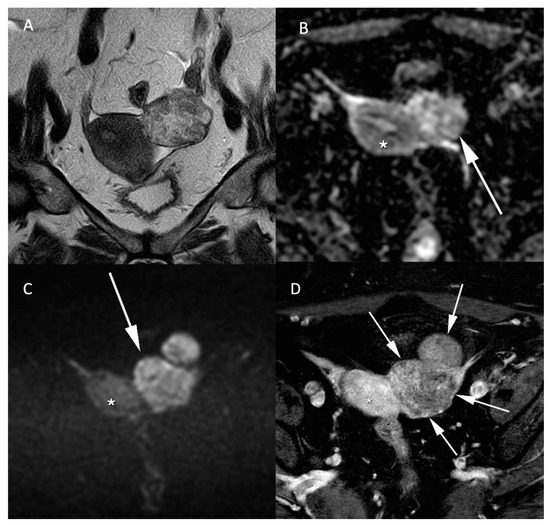

Figure 5.

Histologically proven left ovary adenocarcinoma in a 64-year-old woman. (A) T2W hyperintense heterogeneous left adnexal mass next to the uterus (*). Tissular bilobed left adnexal mass with parts of low (B) ADC values and high (C) b-1000 signal consistent with a diffusion restriction in the lesion (C). Post injection of gadolinium (D) T1W sequence with fat-saturation shows a heterogeneous enhancement (arrow).